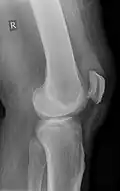

Quadriceps tendon rupture in plain X-ray -

X-ray of a tear of the patellar tendon. On the left: The kneecap is pulled up. On the right: Significant dent in the soft tissue above the kneecap. -